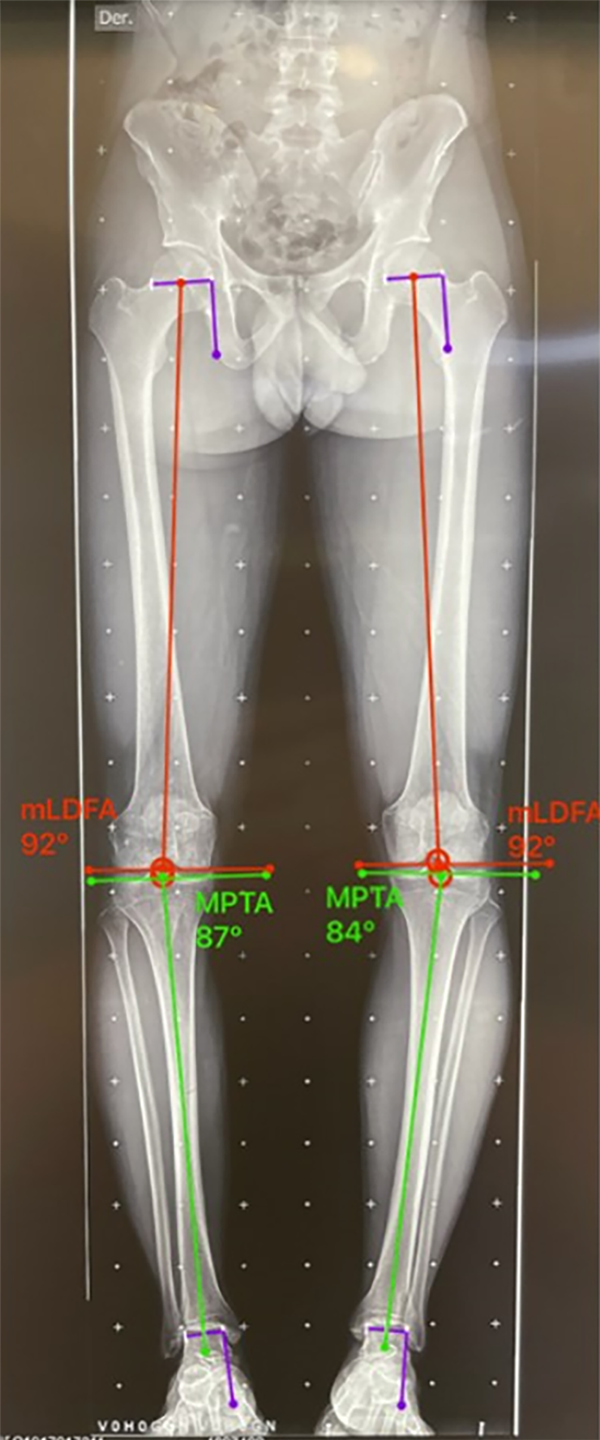

Figura 4: Ángulo femoral distal lateral mecánico (mLFDA): mLDFA y MPTA bilateral, se observa del lado izquierdo una deformidad en varo del fémur 92° (normal 85-90°) y la tibia 84° (normal 85-90°). Lado derecho con una deformidad en varo del fémur 92° y la tibia 87° en valor normal.